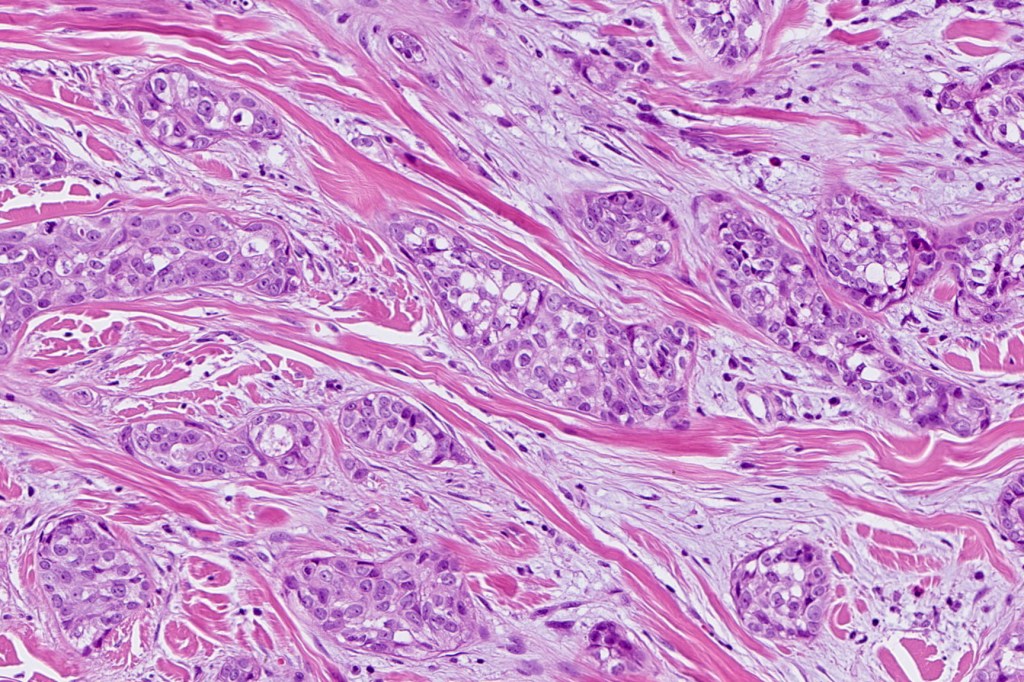

•Widely infiltrating biphasic tumor

•Superficial SCC

•Adenocarcinoma in deeper reaches

•Variable pleomorphism and mitotic activity

•Deep part may show both ducts and glands

•Often extends to the subcutaneous fat

•Perineural infiltration is commonly seen